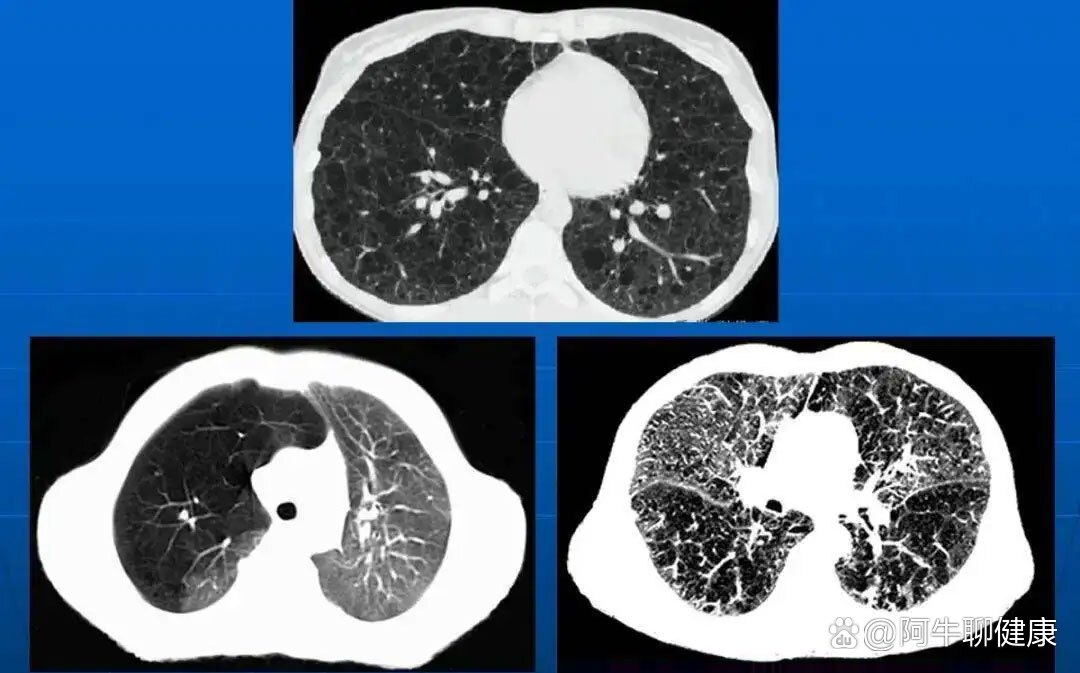

满目疮痍→记录一例慢阻肺合并ipa的疑问 - 丁香园论坛

肺气肿ct分型